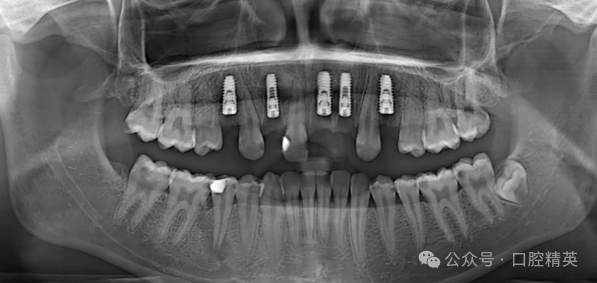

义齿种植是当前牙缺损缺失患者最常用的治疗方法,分为常规种植和即刻种植修复。

需要患者拔牙后到3到6个月再植入种植体,种植后3~6个月进行二期手术,完成冠修复。同时牙齿拔除后等待过长时间易导致牙槽骨量不均匀,影响种植效果。

新型口腔种植技术,即在牙齿拔除后即刻植入种植体并有效保存患者正常的牙槽骨高度和宽度,该种修复方法可以大大缩短患者的治疗时间,可快速形成种植床。

不翻瓣技术外科操作少,后期缝合时间短,但是该技术操作过程中因为无法将黏骨膜瓣翻开,因此医生无法对牙槽骨形态进行直接观察,只能依靠以往的临床经验对种植体植入方向进行判断,导致患者唇侧骨壁有穿孔风险,这就需要术前对患者是否具有不翻瓣技术修复适应证进行明确,以保证手术安全性和术后种植体成功率、稳定性。